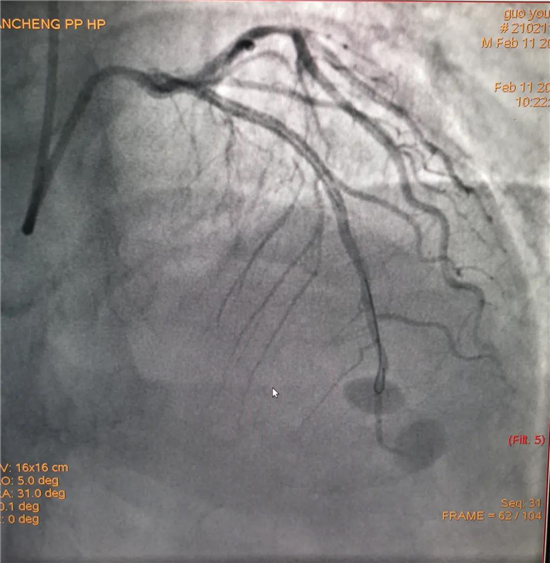

除夕,郭先生無明顯誘因突發(fā)胸痛,120急救人員到達(dá)現(xiàn)場,心電圖顯示:竇性心律完全性束支傳導(dǎo)阻滯。信息立刻發(fā)送到胸痛中心介入微信群中,心內(nèi)科值班醫(yī)生初步診斷為急性廣泛前壁心肌梗死,必須盡快進(jìn)行急診支架治療,開通血管。值班醫(yī)生電話指導(dǎo)院前治療,并立即啟動胸痛綠色通道,24小時(shí)備班的介入治療團(tuán)隊(duì)立即到位,9:30患者被送到導(dǎo)管室行冠脈介入診療,9:40急診PCI手術(shù)隨之開始,冠脈造影檢查提示左前降支閉塞,植入支架,堵塞的血管被順利打通,患者癥狀緩解,手術(shù)非常成功,10:20患者被送往病房進(jìn)一步治療。